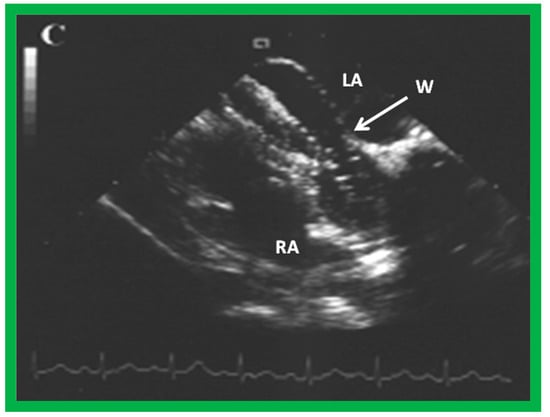

9.7. Thrombus Formation